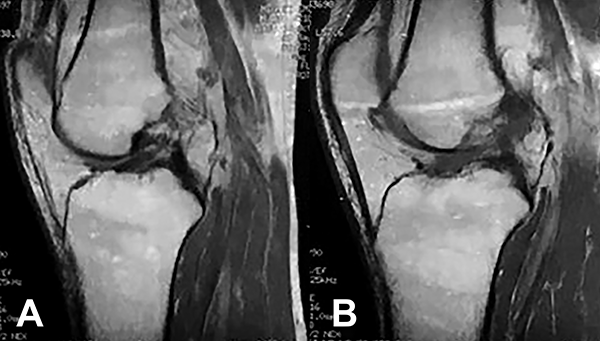

El LCA derecho se lesionó en febrero de 2017 y el izquierdo en febrero de 2018, treinta meses y seis meses, respectivamente, antes de la redacción del presente trabajo. En ambas situaciones, el mecanismo lesional fue flexión, rotación y valgo de rodilla sin contacto durante la práctica deportiva. Del examen físico se destaca una disminución muscular a predominio de muslo izquierdo, sin derrame articular a nivel de rodillas. Se comprueba un rango completo de movimiento en maniobras pasivas y activas, con dolor en el sector posterior de rodilla izquierda a la flexión máxima (5/10 EVA). Lachman positivo bilateral, maniobras meniscales impresionan negativas (fig. 1).

Figura 1: Imágenes de RM, corte sagital. Obsérvese la lesión del LCA en rodillas derecha (a) e izquierda (b).